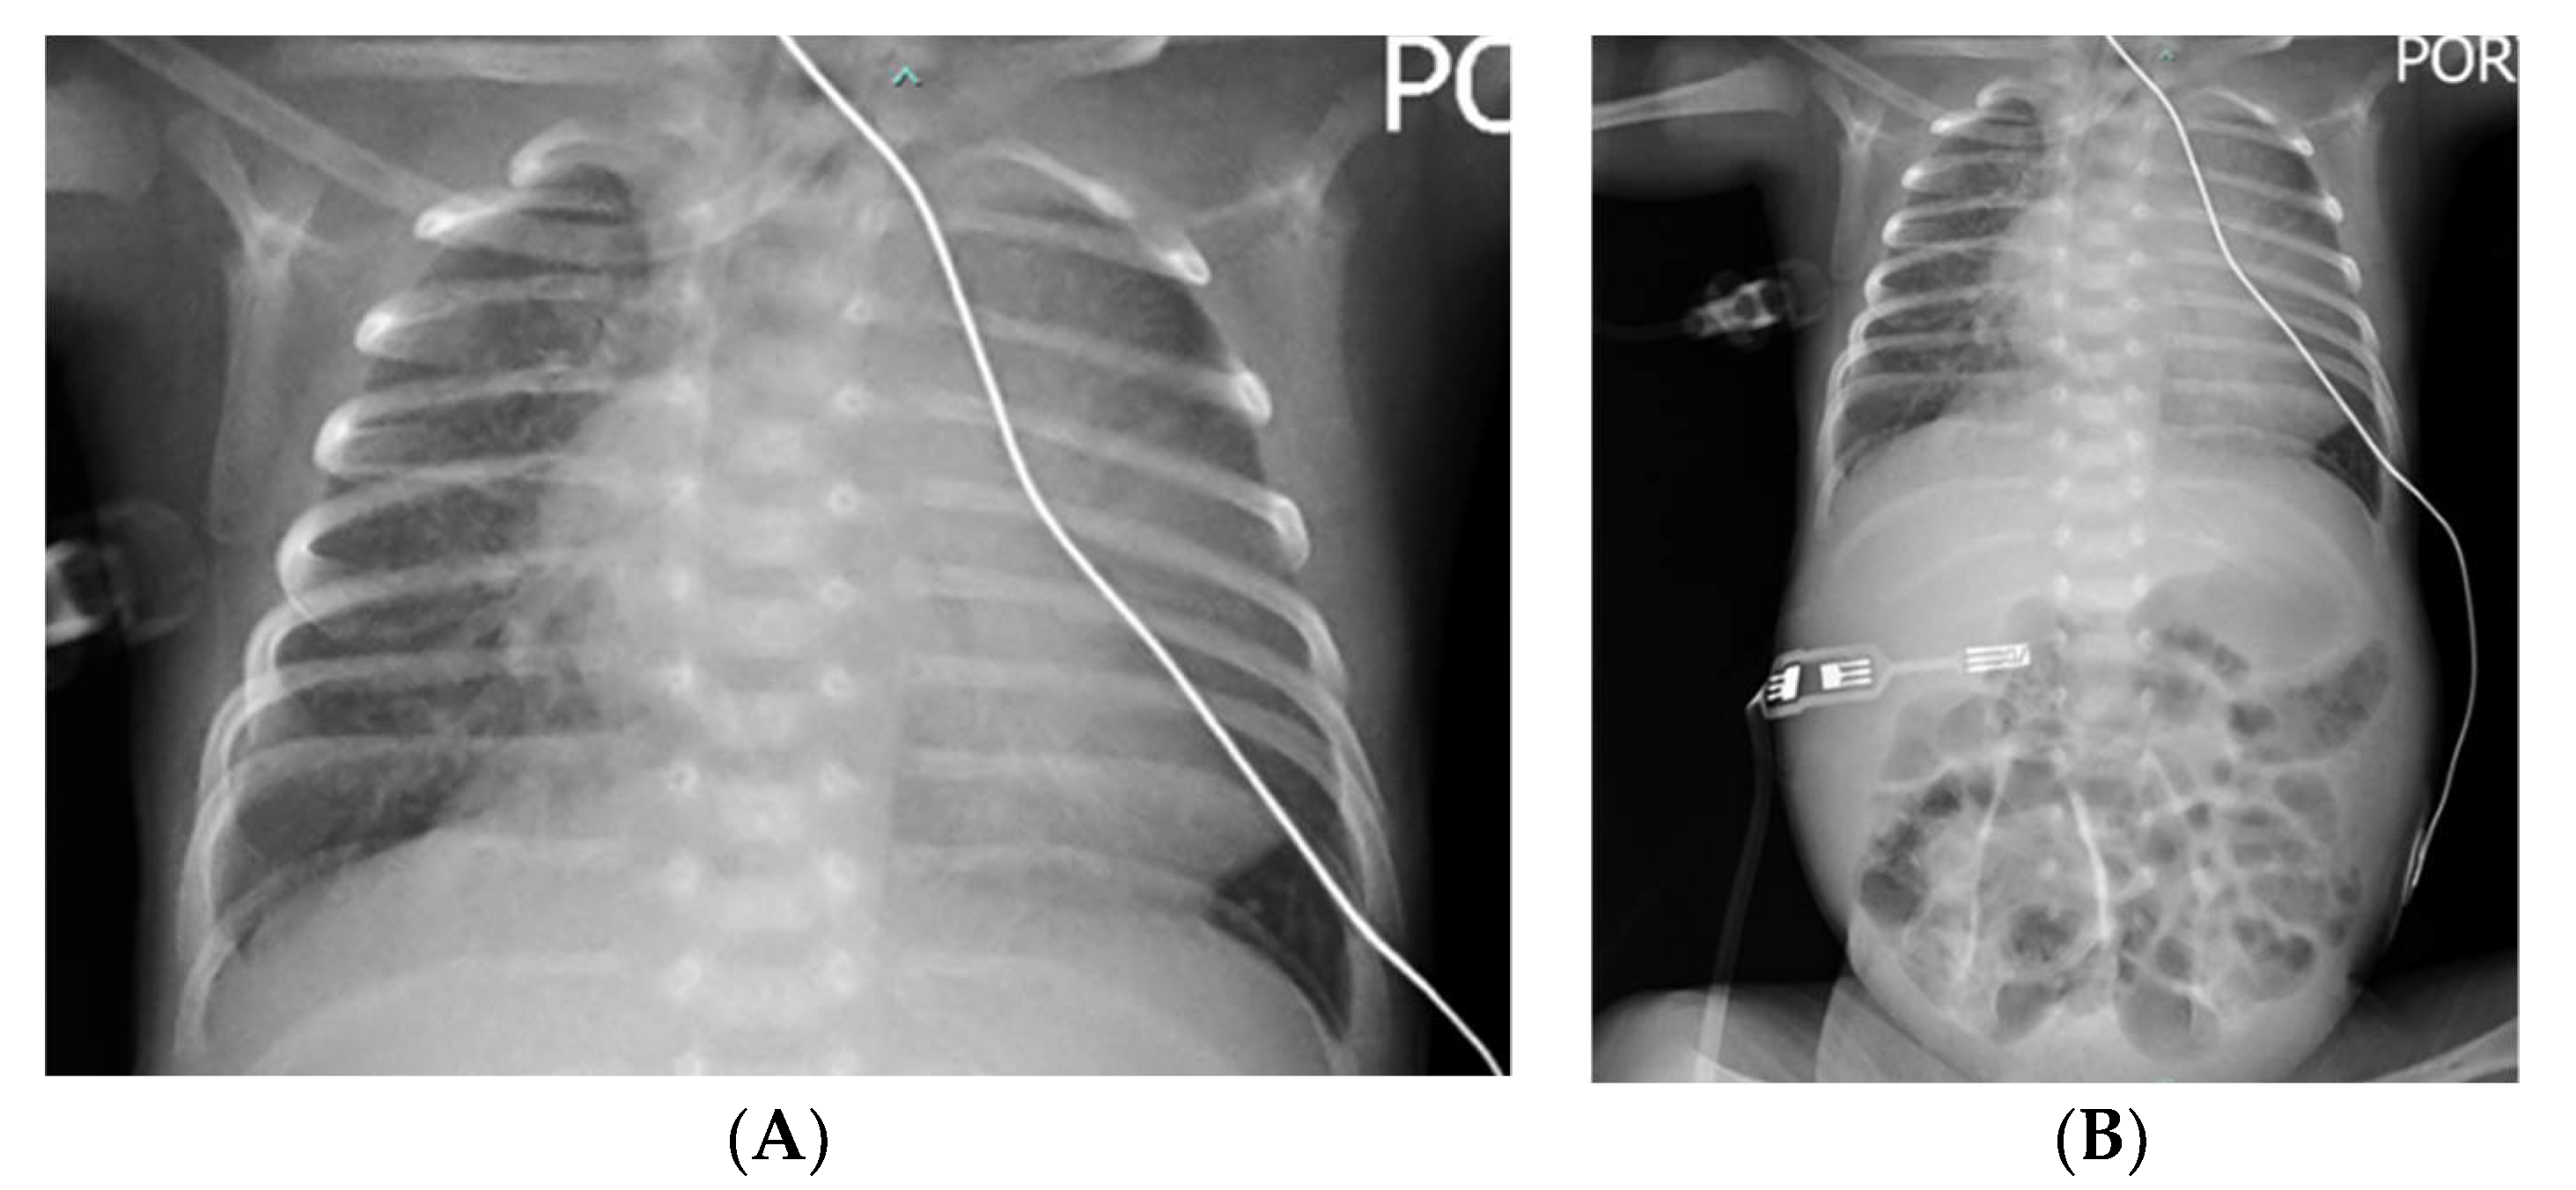

2. Case Presentation